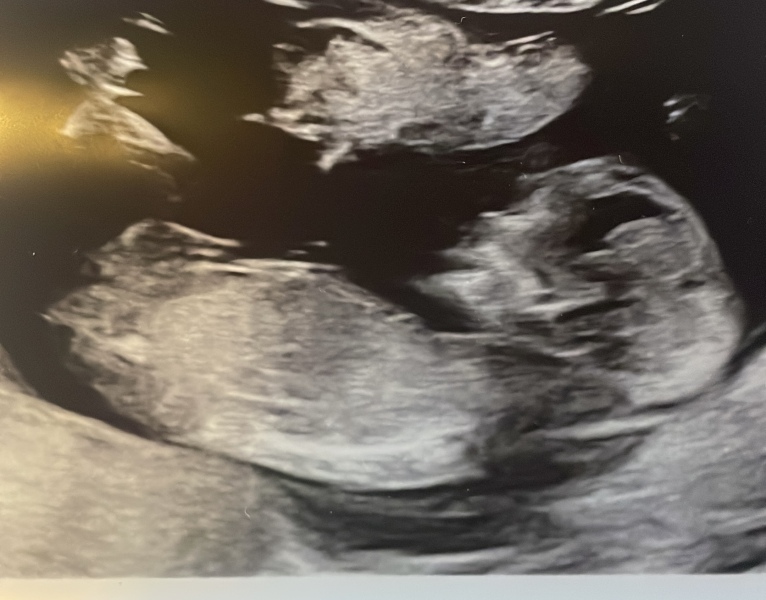

Nub? Is there no nub? Anyone got any guesses

Hello! I am expecting a 3rd (yikes!) and none of mine of my husbands family have girls so there is a lot of pressure. We are going to find out in a few weeks but just wanted to see what people thought? I’m happy with either but feeling the pressure to produce a girl 😬🫣. I have A LOT of photos. Asked for 2 but got 5 so I’ll post them all 😂